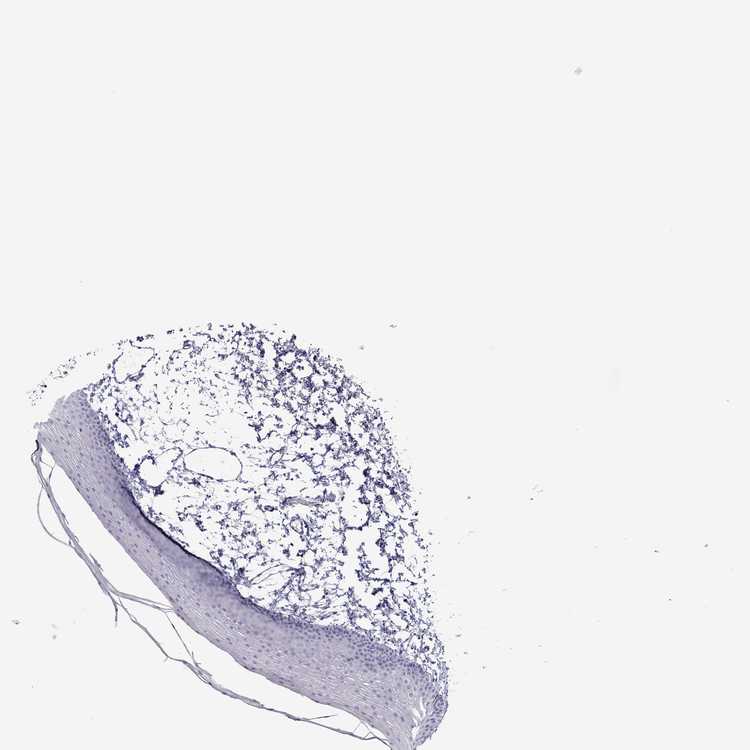

TISSUE PRIMARY DATA ORAL MUCOSA Show tissue menu

ORAL MUCOSA - Antibody stainingi

Antibody staining in the annotated cell types in the current human tissue is reported as not detected, low, medium, or high, based on conventional immunohistochemistry profiling in selected tissues. This score is based on the combination of the staining intensity and fraction of stained cells.

Each image is clickable and will lead to virtual microscopy that enables deeper exploration of all samples and also displays staining intensity scores, fraction scores and subcellular localization as well as patient and tissue information for each sample.

Antibody HPA076764

Squamous epithelial cells Not detected